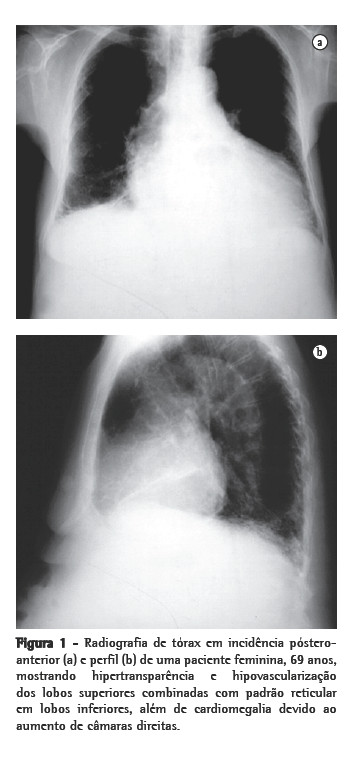

Todos os pacientes tinham achados compatíveis com enfisema e FPI na radiografia de tórax e na TCAR (Figuras 1 e 2). Áreas de radiotransparência em lobos superiores foram encontradas em todos os casos. Opacidades reticulares em bases pulmonares estavam presentes em 6 casos. Apenas 2 pacientes não apresentavam faveolamento. Em 4 casos evidenciaram-se áreas de atenuação em vidro despolido. Bronquiectasias de tração foram descritas em 3 dos 11 casos.